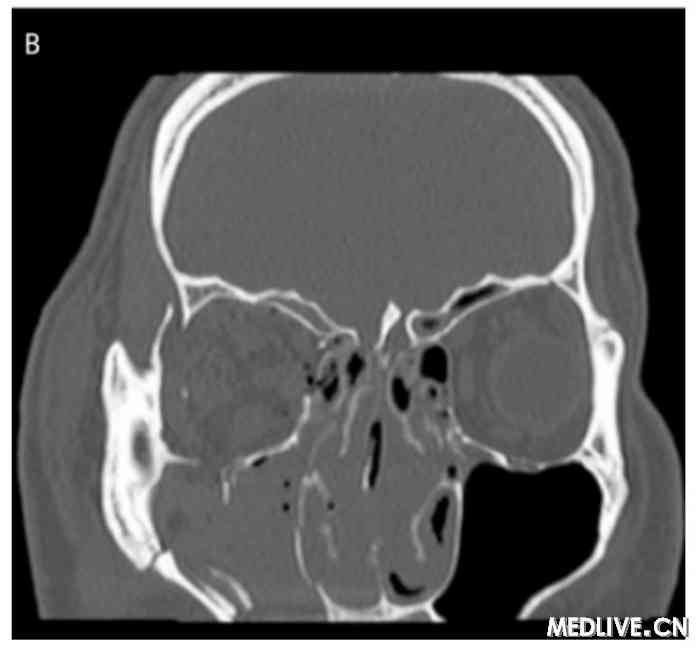

双眶三维CT 右侧眼球外突双眶三维CT 右眼眶下壁骨折

图2 双眶三维CT

A:右眼球外突,考虑存在右眼肌群及视神经损伤。右侧玻璃体内稍高密度影,出血可能性大。双侧上颌窦、筛窦、蝶窦及右侧额窦内积液;

B:右眼眶下壁骨折。